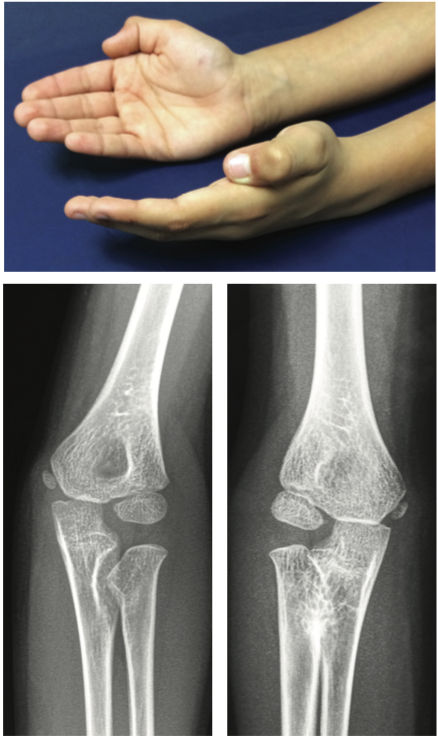

Michael W. Cater, MD

A 7-year-old boy was brought to the office by his mother because he was unable to fully turn the palm of either hand into the flattened, or supinated, position.